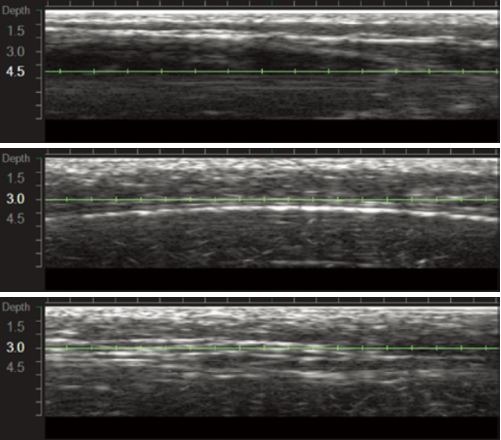

실제 우리 병원에서 울쎄라를 진행하는 모습입니다.

울쎄라의 시술 과정을 찾아보시면 위와 같이 핸드피스를 피부에 접촉한 후 부드럽게 쉐이빙하는 모습을 보셨을 겁니다. 이는 울쎄라에서 출력되는 에너지를 전달하기 위한 과정이라고 보면 되는데요.

울쎄라의 경우 다른 초음파 리프팅 장비들과 다르게, DeepSee 라는 초음파 기술로 환자분의 피부층을 직접 확인하면서 시술이 가능한데요.

울쎄라 초음파 화면을 보면 단순히 피부층만 확인하는 것이 아니라 다양한 정보들을 파악할 수 있는데요.

1. 피부와 트랜드듀서(핸드피스)가 밀저하게 접촉되었는지?

2. 에너지가 타겟층에 제대로 전달되는 있는지?

3. 시술 전 젤을 너무 과하게 바르지 않았는지?

위와 같은 부분들을 실시간으로 체크하면서 에너지를 좀 더 효율적이고 정확하게 전달할 수 있습니다.

이러한 과정의 차이가 결과적인 차이도 만들구요.